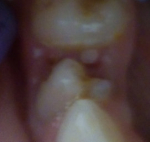

Сколько зубов должно быть в 2 года у ребенка?

Педиатры называют нормой для двухлетнего ребенка наличие 20 молочных зубов, которые располагаются по 10 на каждой челюсти крохи. Тем не менее, у некоторых деток последняя четверка зубов (вторые моляры) может еще не прорезаться. И потому наличие 16 зубов в 2-летнем возрасте также является нормальным. Эти зубы зачастую прорезываются в возрасте 20-26 месяцев на нижней челюсти и в возрасте 26-33 месяцев вверху. Именно поэтому у некоторых двухлеток их может не быть.